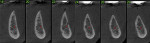

A 69-year-old female patient presented with a request for implants to replace the posterior left mandibular teeth that had been missing for several years. A CBCT was taken and cross-sections were analyzed in planning for implant placement. Adequate width was noted mesial to the mental foramen, but inadequate width was revealed distal to the mental foramen (Figure 11). The area was flapped and two implants were placed mesial to the mental foramen. A surgical bur was used to perforate the lateral aspect of the ridge distal to the mental foramen to create bleeding points (Figure 12). Bond Apatite was mixed and placed over the previously perforated bone and over the implants that had just been placed (Figure 13).

Following 4 months of healing to allow the graft to mature and organize, a CBCT was taken. Cross-sectional slices demonstrated a ridge width increase in the area distal to the mental foramen that would allow implant placement (Figure 14). The area was flapped, osteotomies were prepared, and implants were placed (Figure 15).